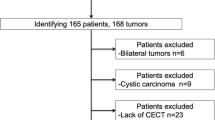

This study included patients who underwent TRAE for biopsy-proven CCRCC between May 2020 and November 2021. All TRAE procedures were performed before cryoablation of CCRCC to enhance safety and treatment efficacy [4,5,6]. Renal 4D-CTA was performed within 4 months before TRAE for procedure planning. Patients who met at least one of the following criteria were excluded: (i) 4D-CTA images did not follow the standard institutional protocol described below; (ii) 4D-CTA images were not evaluable due to poor breath-hold or absence of 1-mm slice images of all phases; and (iii) tumor feeders could not be determined on procedural images. Figure 1 shows the flowchart of patient selection. A total of 41 patients underwent TRAE for biopsy-proven CCRCC. Of these, 19 were excluded due to missing preprocedural 4D-CTA data (n = 8), images unsuitable for evaluation due to poor breath holding (n = 2), missing 1 mm slice data of all phases (n = 8), or inability to identify tumor feeders on procedural images (n = 1). Thus, we analyzed data from 22 patients (male, n = 16; female, n = 6; mean age ± standard deviation [SD], 67.2 ± 9.5 y) with 22 tumors (mean diameter ± SD, 20.0 ± 7.1 mm). Fourteen and eight tumors were respectively nourished by single and dual feeders. Therefore, we analyzed 30 feeding arteries. Table 1 summarizes the characteristics of the patients and tumors.